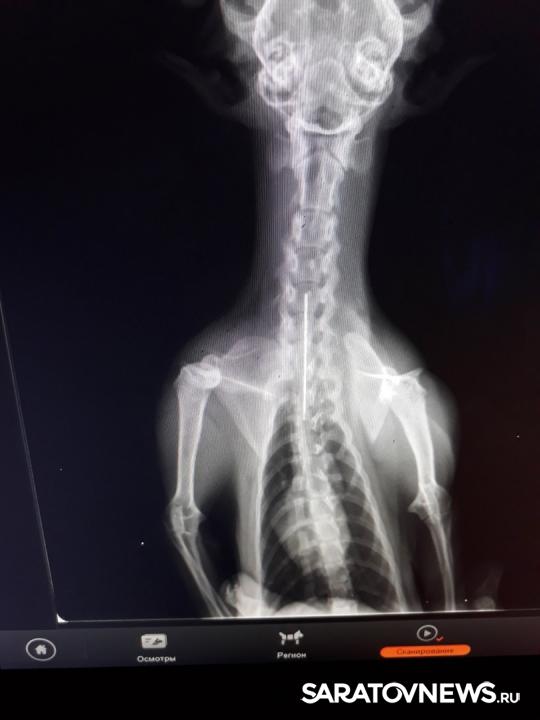

В ветеринарную лечебницу № 1 обратилась женщина, чья кошка сильно кашляла. По словам хозяйки, животное прошло курс лечения в другой клинике по поводу бронхопневмонии, но так и не выздоровела. В ходе диагностики был сделан снимок, на котором было ясно видно, что в мягких тканях шейно-грудного отдела между пищеводом и трахеей находилась игла.